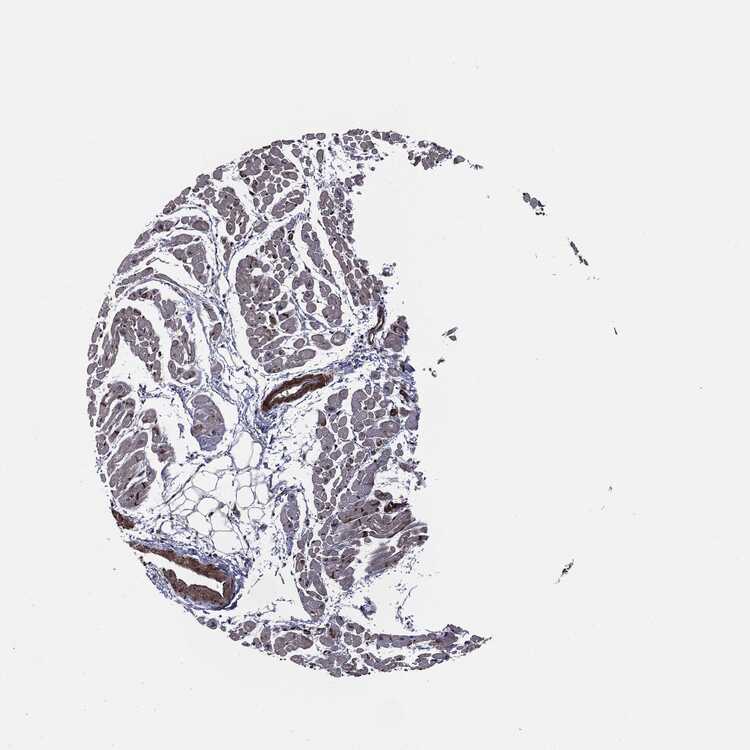

TISSUE PRIMARY DATA HEART MUSCLE Show tissue menu

Heart muscle

Heart

HEART MUSCLE - Expression summary

Protein expression

Heart musclei

On the top, protein expression in current human tissue, based on all annotated cell types, is reported with the units not detected (n), low (l), medium (m) and high (h). Underneath, protein expression in each annotated cell type are reported using the same units.

Protein expression data is based on knowledge-based annotation. For genes where more than one antibody has been used, a collective score is set.

If knowledge-based annotation could not be performed for a gene, no data is displayed here. View antibody staining data further down this page.

Cardiomyocytes: Low

HEART MUSCLE - Antibody stainingi

Antibody staining in the annotated cell types in the current human tissue is reported as not detected, low, medium, or high, based on conventional immunohistochemistry profiling in selected tissues. This score is based on the combination of the staining intensity and fraction of stained cells.

Each image is clickable and will lead to virtual microscopy that enables deeper exploration of all samples and also displays staining intensity scores, fraction scores and subcellular localization as well as patient and tissue information for each sample.

Antibody HPA005695Antibody CAB022068Antibody CAB035999Antibody CAB080052Antibody CAB080054Antibody CAB080098

Cardiomyocytes Not detectedNot detectedLowLowHighHigh